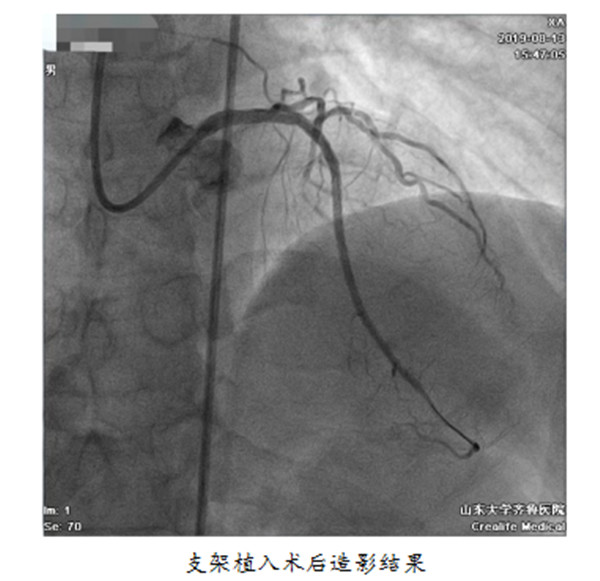

【本站讯】近日,心内科安贵鹏、孟晓副主任医师在李继福主任医师指导下,完成了利用正向夹层重回真腔技术(antegrade dissection re-entry, ADR)开通的高难度冠脉慢性闭塞(chronic total occlusion, CTO)病变,目前病人已痊愈出院。经检索,该术为山东省首例。

ADR技术是近年来备受欧美专家推崇的一种新型高效的CTO开通技术。与传统术式相比,成功高,明显地缩短了手术时间,减少了外科手术的必要。此项技术的开展,标志着绿帽社 正式跻身于少数可以开展所有CTO手术的医疗中心之列,为更多的冠心病患者带来福音。